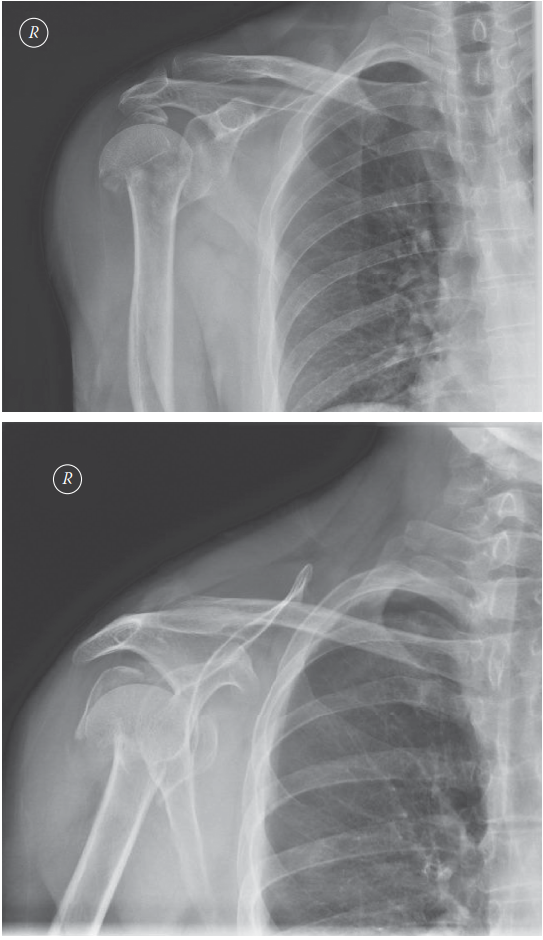

Management of Proximal Humerus Fracture 1. Describe these radiographs. Show Answer Show Explanation 2. How wo…

You are called to the emergency department to see a 60-year-old man who has fallen while running, injuring hi…

A 45-year-old man with epilepsy is brought to the emergency department following a sei- zure. He complains of…